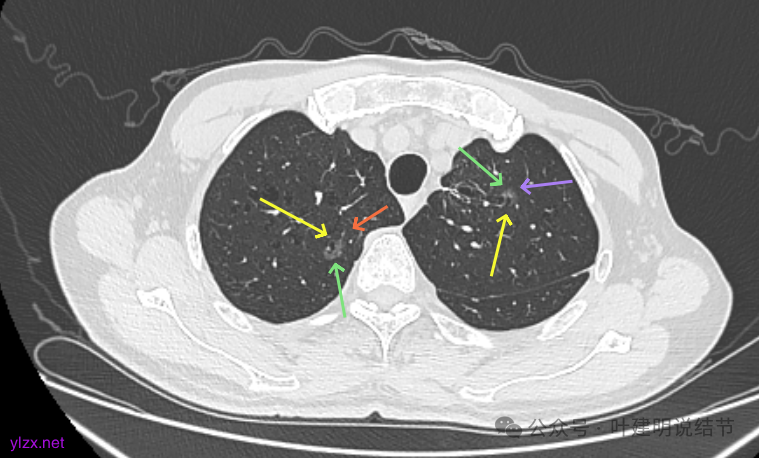

再看2024年9月的:

右上的较前略增大,且有空泡征较豙明显些,肿瘤的成分仍是纯磨密度。

左上病灶也是较为纯的,边缘不光滑,大小似乎略大一点点,不太显著。

最后看2025年3月的连续层面的影像细节:

右上病灶淡磨密度,有空泡征,整体轮廓较清。

瘤肺边界清楚,空泡征明显。

表面不平,没有实性成分。灶内空泡有些像蜂窝状。

病灶边上有小血管走行,整体轮廓清,没有明显实性成分。

右上病灶淡而纯主要原因,空泡征明显。

左上病灶淡而纯,有微小血管进入。

右上淡磨,轮廓清,空泡明显。

左上的小而局部有细支气管扩张的样子,部分边缘显毛糙,有细毛刺样征。

右上叶病灶有血管贴边,轮廓清;

左上病灶纯磨,轮廓清。

右上淡磨,左下密度较右侧的稍不均一点。